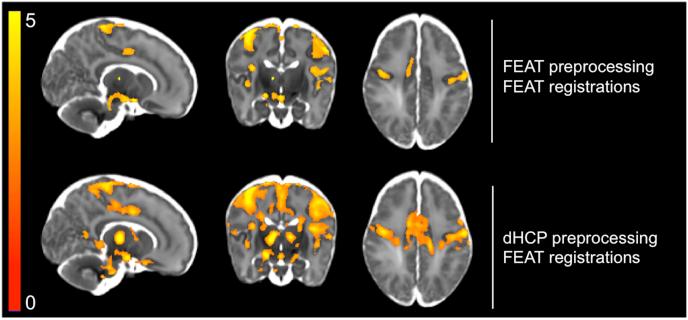

The infant brain is unlike the adult brain, with considerable differences in morphological, neurodynamic, and haemodynamic features. As the majority of current MRI analysis tools were designed for use in adults, a primary objective of the Developing Human Connectome Project (dHCP) is to develop optimised methodological pipelines for the analysis of neonatal structural, resting state, and diffusion MRI data. Here, in an independent neonatal dataset we have extended and optimised the dHCP fMRI preprocessing pipeline for the analysis of stimulus-response fMRI data. We describe and validate this extended dHCP fMRI preprocessing pipeline to analyse changes in brain activity evoked following an acute noxious stimulus applied to the infant's foot. We compare the results obtained from this extended dHCP pipeline to results obtained from a typical FSL FEAT-based analysis pipeline, evaluating the pipelines' outputs using a wide range of tests. We demonstrate that a substantial increase in spatial specificity and sensitivity to signal can be attained with a bespoke neonatal preprocessing pipeline through optimised motion and distortion correction, ICA-based denoising, and haemodynamic modelling. The improved sensitivity and specificity, made possible with this extended dHCP pipeline, will be paramount in making further progress in our understanding of the development of sensory processing in the infant brain.